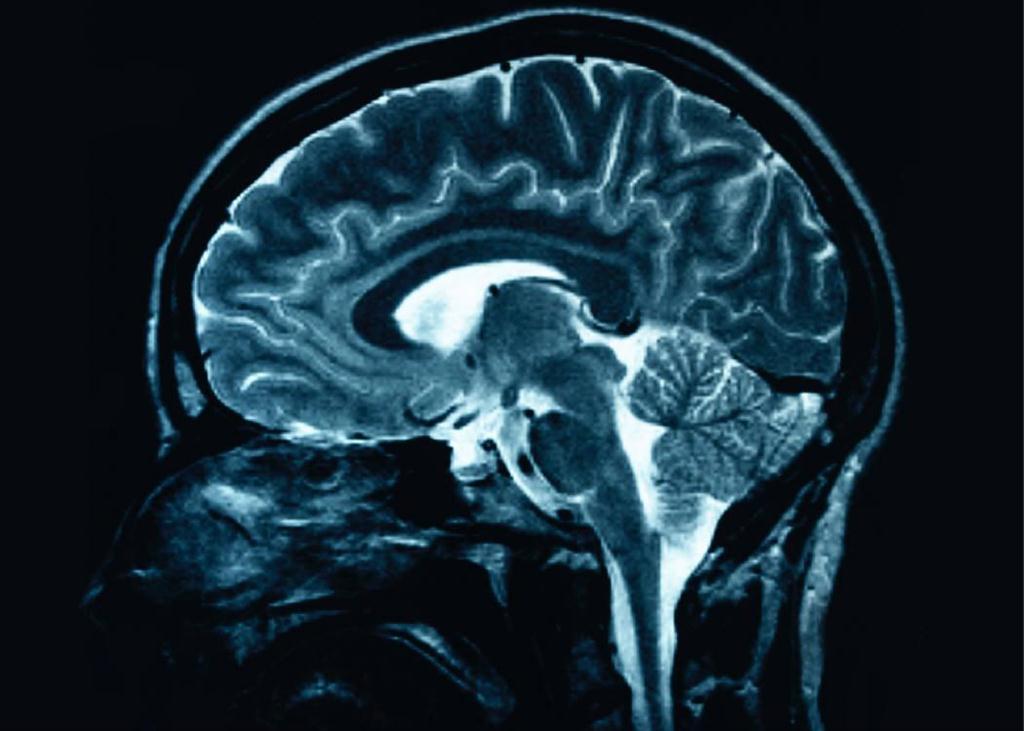

But even more astounding, chronic pain is associated with reduced brain gray matter and impaired cognitive ability to think and reason. (4) But there is good news: Reduction of chronic pain shows brain regeneration. (4)